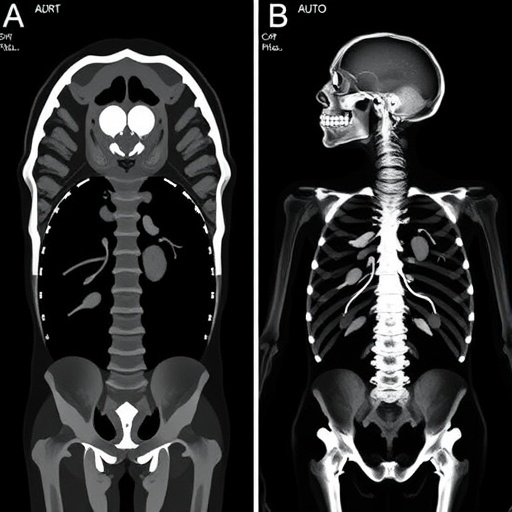

First and foremost, PMCT demonstrated superior sensitivity in detecting certain types of complex fractures, particularly subtle cranial and facial fractures that are often challenging to discern visually. The three-dimensional reconstructions generated by PMCT allow forensic radiologists to examine bony structures layer by layer without dissection, revealing minute fractures that may be obscured during autopsy due to tissue distortion or restricted access. This advanced imaging capability marks a significant step forward for forensic radiology, emphasizing the potential of non-invasive methods to enhance diagnostic accuracy.

Conversely, the study also identified unique advantages of traditional autopsy, particularly in the assessment of soft tissue injuries accompanying fractures. While PMCT excels at skeletal visualization, its ability to detect periosteal or ligamentous damage and subtle hemorrhagic changes remains limited compared to direct visual and tactile examination. The meta-analysis highlights that a hybrid approach—utilizing PMCT as an adjunct rather than a replacement—may yield the most comprehensive forensic assessment, preserving the strengths of both modalities and mitigating their individual shortcomings.